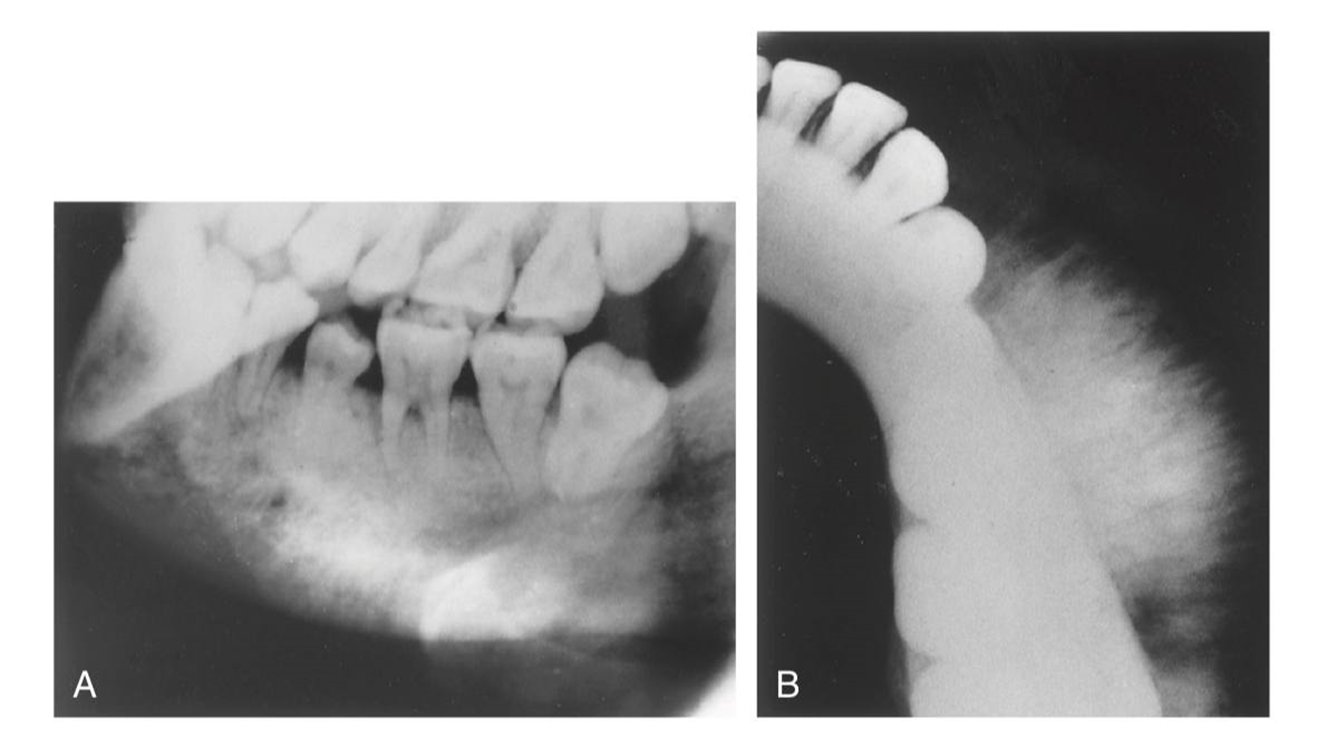

1. Mary is a 67-year-old who was referred to the periodontist. As part of the adiographic examination, this small radiolucent lesion was detected. The teeth were vital. Considering the patient’s age and the location, size, and clinical findings, what is your diagnostic impression?

2. Bill is an asymptomatic 47-year-old who presented for routine dental treatment. This radiograph was taken as part of the full mouth survey.

What is your diagnosis?